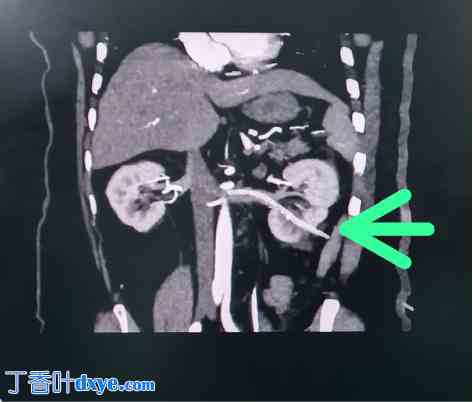

图2

2.jpg

CT扫描显示左肾静脉内有肾造瘘管。